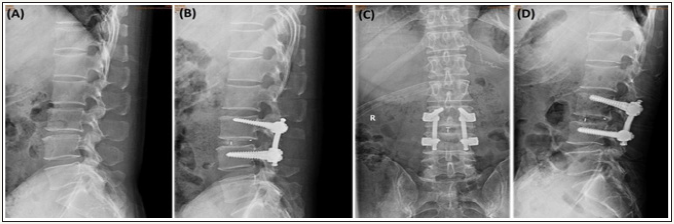

Figure 7: A 48 years old female with isthmic spondylolisthesis at L5-S1 level,

(A) Preoperative Lateral radiograph showed that slippage was 31.6% and focal lordosis was -2.88.

(B) and (C) 6 months follow-up lateral and anteroposterior X-ray showed that complete reduction of the spondylolisthesis.